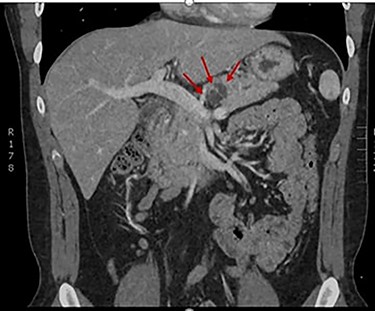

The patient received vaccinations preoperatively against encapsulated organisms to include Streptococcus pneumoniae, haemophilus influenzae type b and meningococcus. A dedicated pancreas protocol computed tomography scan was performed for operative planning, which demonstrated interval increase in the size of the cyst to 2.4 cm (Fig. 2). On the day of surgery a robotic-assisted laparoscopic distal pancreatectomy was performed. We elected to perform a splenectomy because the splenic vasculature was found to be densely adhered to the posterior aspect of the pancreas secondary to repeated bouts of pancreatitis. The distal pancreas and spleen specimen, along with 21 lymph nodes, were removed en bloc. Final pathology demonstrated a 1.4 cm IPMN with low-grade dysplasia involving the branch ducts and focal high-grade dysplasia involving the main duct. No invasive malignant component was identified in the specimen and all examined lymph nodes were benign. The patient had an uncomplicated recovery and was discharged on postoperative Day 5 following drain removal. Completion of his post-splenectomy vaccinations were confirmed at his initial follow-up clinic visit. The patient will report for an additional follow-up with active surveillance imaging in 6 months.

CT demonstrating resolution of pancreatitis and interval growth of IPMN to 2.4 cm.